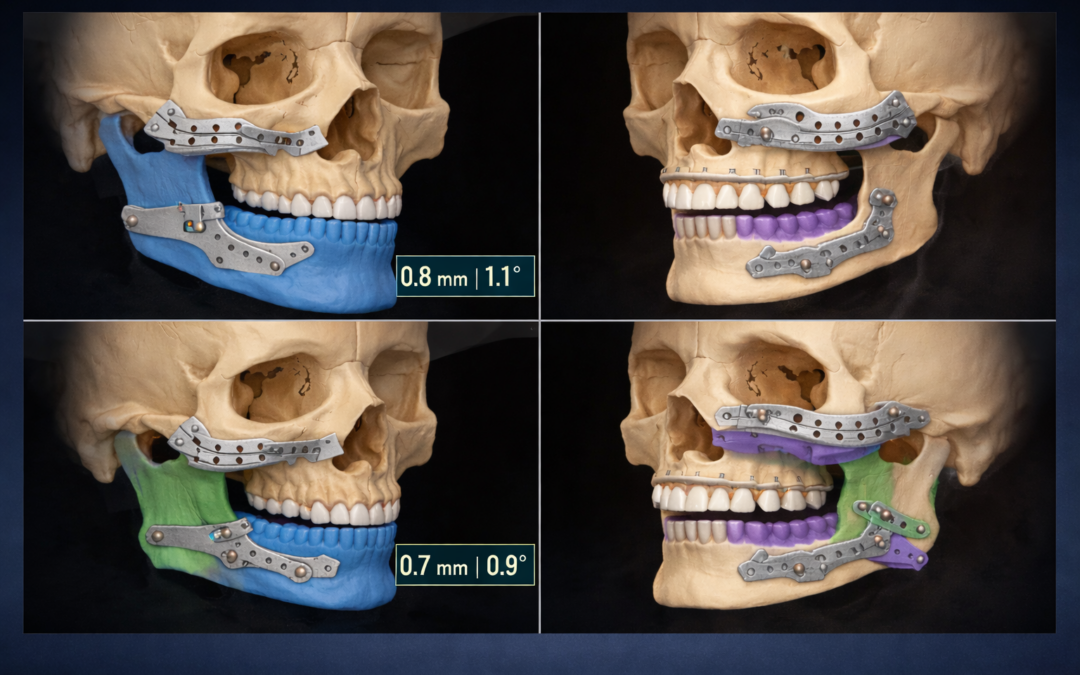

Does Surgical Sequencing Still Matter in Fully Digital Bimaxillary Orthognathic Surgery?

A Retrospective Accuracy Study of 46 PSI‑Guided Cases

Yildirim A., Hertach R., and Yildirim V.

Digital precision meets clinical decision-making: This study shows that in PSI-guided bimaxillary orthognathic surgery, both mandible-first and maxilla-first sequences achieve equally high accuracy. Virtual surgical planning ensures predictable, patient-specific outcomes, highlighting that technology can transcend traditional sequencing debates.